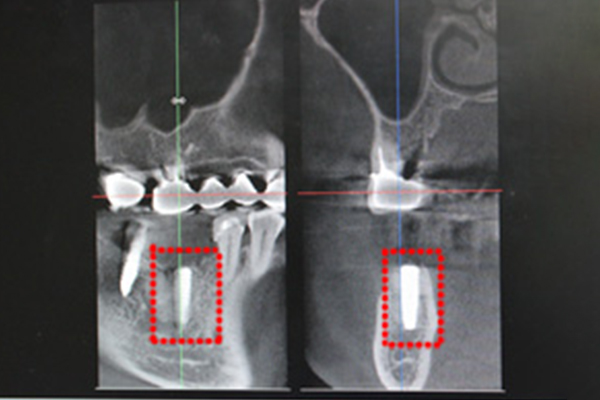

CGFで骨が出来たところにインプラントを埋入します。